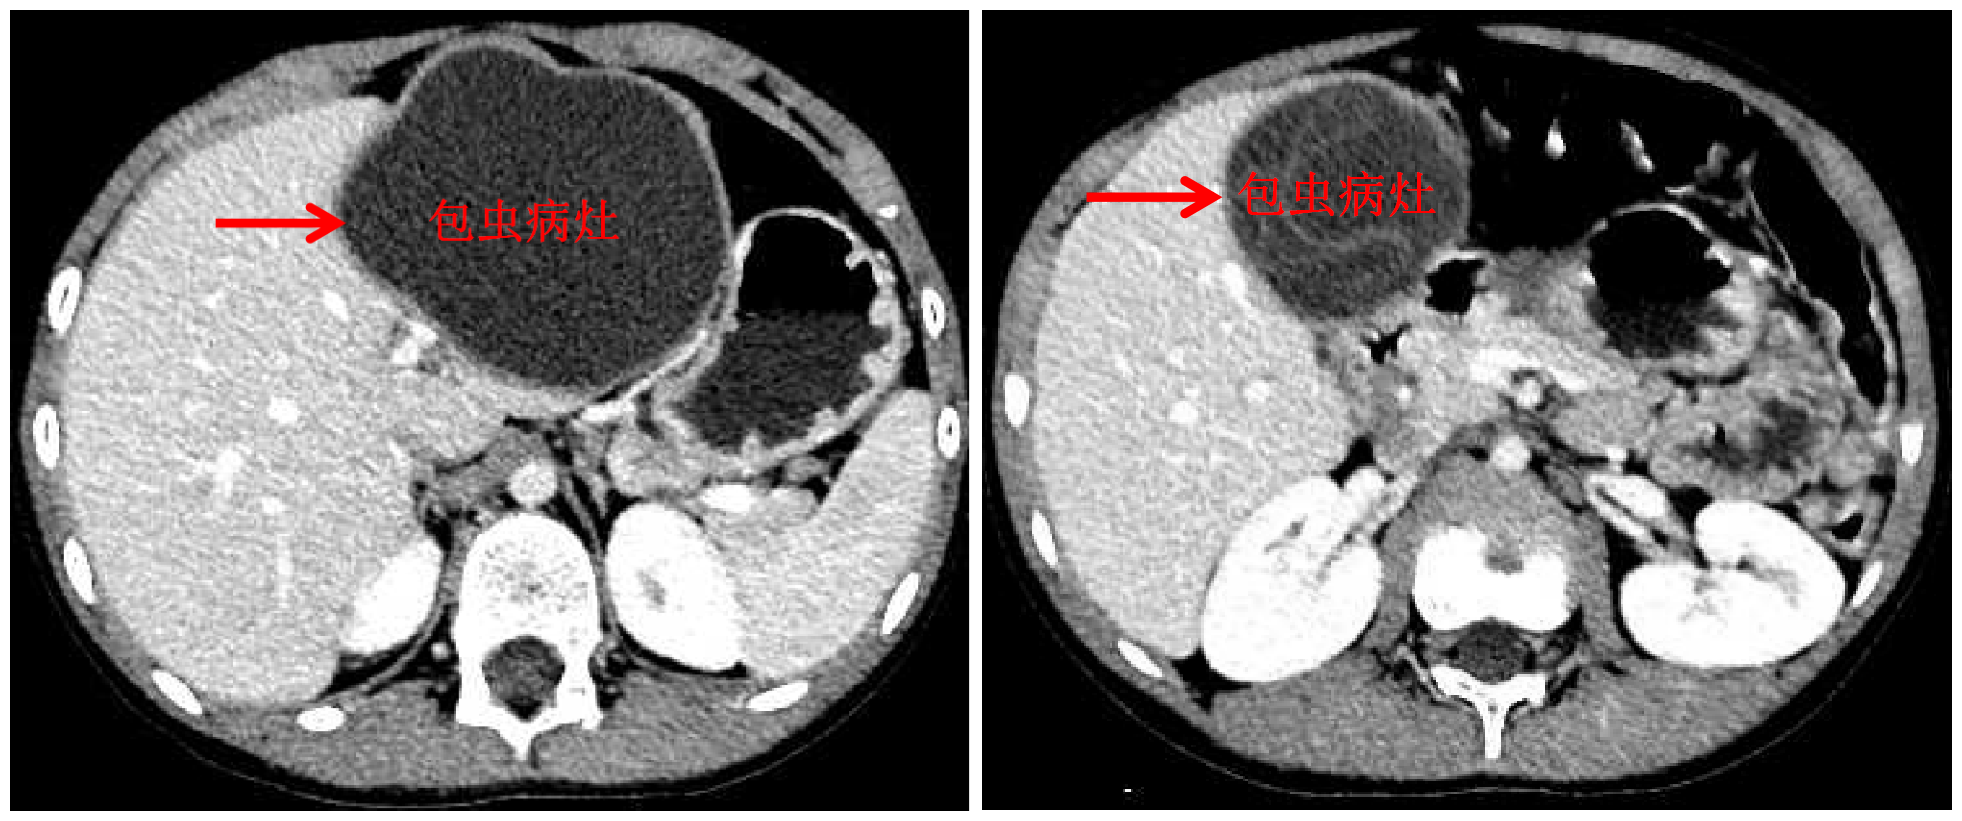

8xbet(中国)网10月13日电 国庆前,8岁的小扎西被父亲带到了西藏大学附属拉萨市人民医院普外科,此次距离孩子确诊肝包虫病已有一年之久。腹部影像显示,小扎西体内的囊型肝包虫病已经侵袭了左肝大部。

包虫病灶